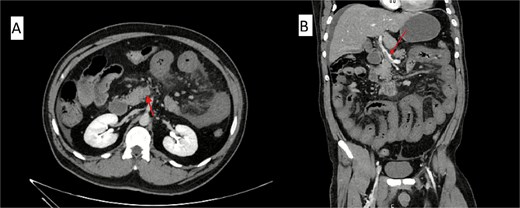

On arrival, his haemoglobin was 7.2 g/dl, WBC 17.5 × 109/L, and CRP 321 mg/L. Electrolytes revealed mild hyponatremia, hypocalcemia, and hypophosphatemia, with preserved renal function. Coagulation studies showed mildly prolonged prothrombin time. Upper endoscopy demonstrated active bleeding beyond the duodenum without an identifiable source. Repeat CT confirmed complete thrombosis of the portal and superior mesenteric veins with small-bowel ischaemia (Fig. 1). Emergency laparotomy revealed extensive jejunal and ileal gangrene, requiring near-total small-bowel resection with end jejunostomy (Video 1).

Contrast-enhanced abdominal CT scan showing acute mesenteric venous thrombosis. (A) Axial view demonstrating complete thrombosis of the superior mesenteric vein (arrow). (B) Coronal view confirming thrombus extension into the portal venous system (arrow).